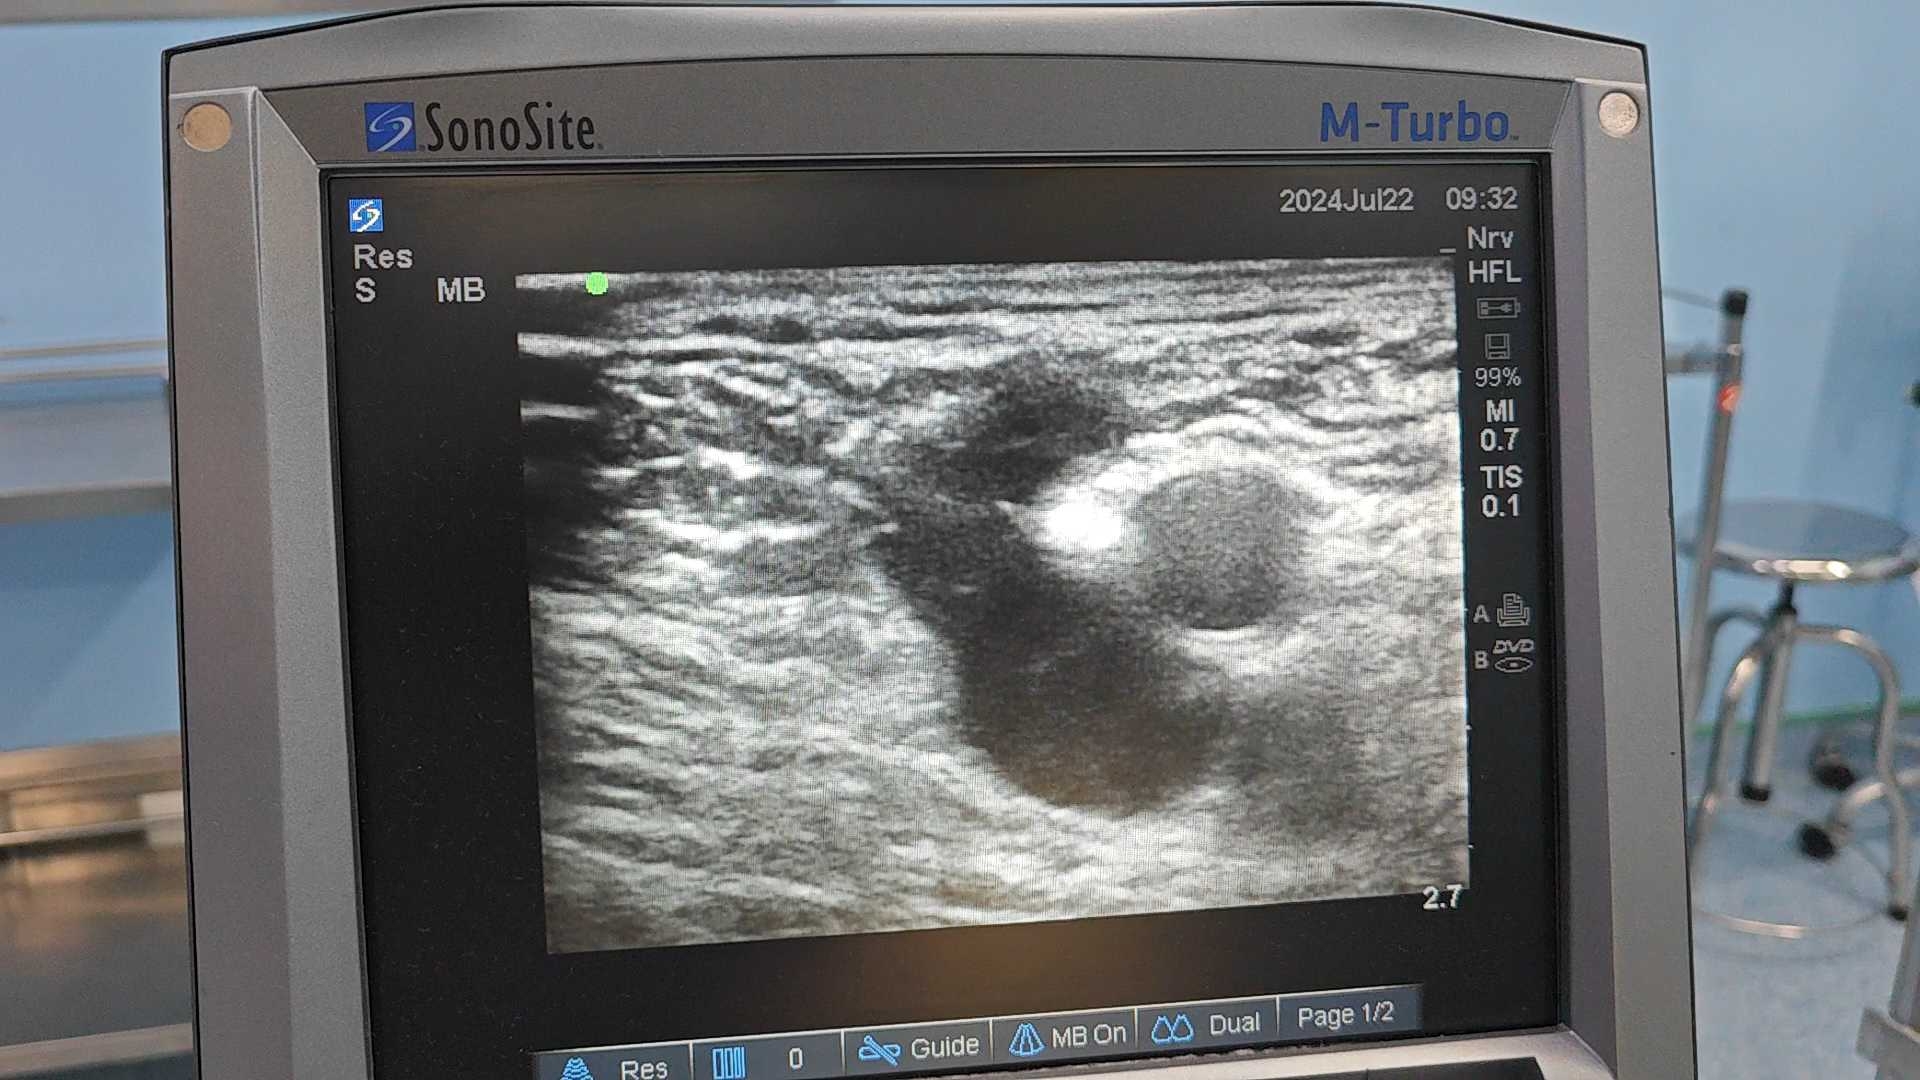

超声评估显示,大隐静脉全程扩张,直径达11mm,反流时间长达4秒,推测原手术可能仅结扎了分支,或未寻及并成功实施高位结扎。因此,我们再次为其进行了左下肢大隐静脉高位结扎剥脱术。

去年9月,一位65岁女性患者因“右下肢浅静脉扩张迂曲20年”入院。初看以为是常规大隐静脉曲张,但超声评估发现,大隐静脉上段管径正常,中段却存在一条直径4mm的病理性穿通静脉反流,导致其下方大隐静脉及属支扩张迂曲。